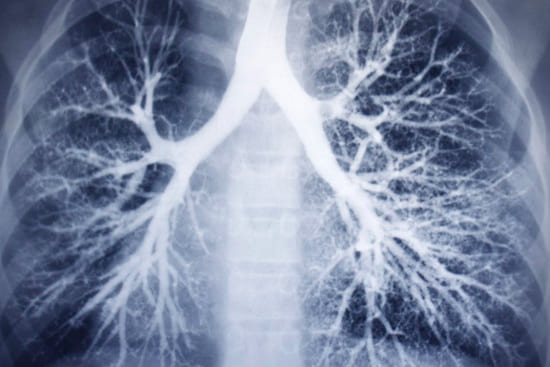

Дефицит альфа-1-антитрипсина (ДАТ) оказывает наиболее разрушительное воздействие именно на легкие, приводя к прогрессирующему повреждению легочной ткани. Основным проявлением этой патологии является развитие эмфиземы, которая часто манифестирует в молодом возрасте и у некурящих людей, а также входит в спектр хронической обструктивной болезни легких (ХОБЛ).

При недостаточности А1АТ легочная ткань теряет свою защиту. Нейтрофильная эластаза начинает бесконтрольно разрушать эластичные волокна, которые формируют стенки альвеол (мельчайших воздушных мешочков в легких). Это приводит к их истончению, разрушению и слиянию, образуя большие полости. Утрата эластичности и разрушение альвеол нарушают газообмен и способность легких эффективно выдыхать воздух, что вызывает одышку и другие симптомы.

Эмфизема легких является наиболее характерным и тяжелым легочным проявлением ДАТ. Она представляет собой необратимое расширение воздушных пространств дистальнее терминальных бронхиол, сопровождающееся разрушением стенок альвеол без выраженного фиброза.

- Тип эмфиземы: Чаще всего развивается панлобулярная (или панацинарная) эмфизема, при которой поражаются все компоненты ацинуса (структурно-функциональной единицы легкого). Это отличает ее от центролобулярной эмфиземы, более типичной для курильщиков, где преимущественно страдают центральные отделы ацинуса.

- Локализация: Повреждение легочной ткани при ДАТ обычно более выражено в нижних долях легких, тогда как при эмфиземе курильщиков чаще страдают верхние доли.

- Компьютерная томография (КТ) легких высокого разрешения: Является наиболее чувствительным методом визуализации для выявления и оценки степени эмфиземы. Она позволяет увидеть характерное панлобулярное распределение и преимущественно нижнедолевую локализацию, а также исключить другие причины легочных симптомов.